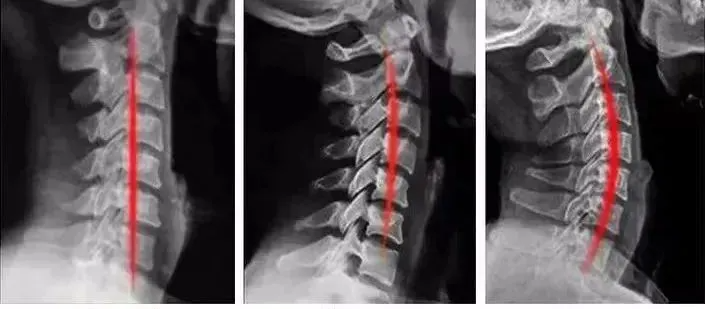

我们的颈椎有一个正常的生理曲度,枕头是维持颈椎生理曲度的重要工具。

枕头太高,颈椎处于一种类似「被动低头」的状态,越睡越直,甚至经常「落枕」。

枕头太低,脖子又会处于过度仰伸的状态,容易影响呼吸系统,出现张嘴呼吸、打鼾等问题。

好枕头的标准:适合你自己的颈椎曲度。优先推荐选择头部和颈部有落差的枕头。

长时间睡这种零压速眠枕,对我们的颈椎是非常友好的,甚至还能帮助我们恢复健康的生理曲线!

小编同事坚持用下来,惊喜的发现,颈椎在慢慢恢复健康的生理曲线,可以说是真正的助眠又护颈的好枕头。